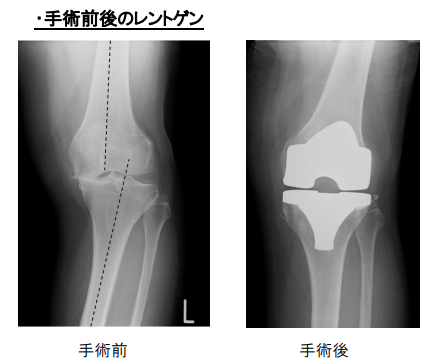

変形性膝関節症、膝関節内の骨壊死に対して施行する人工関節と骨切りの手術は

膝の変形の程度、下肢のアライメント(O脚かX脚か)、膝の可動域、靭帯損傷の有無、患者さんの年齢、体格、活動度などにより手術方法を選択します。

高位脛骨骨切り術はO脚で荷重軸が内 側に傾いており、靭帯(じんたい)などが健康で関節の温存が可能で膝関節の内側だけが悪い場合に、骨を切ってO脚をX 脚に矯正して痛みを取る手術です。適応の条件として、骨がある程度しっかりしていることが必要ですので、おおむね70歳以下で活動性の高い方 が対象となります。ご自分の関節が残りますからスポーツなども可能です し、手術後に万一悪化したとしても、人工膝関節全置換術に移行できるのもメリットです。

人工膝関節単顆置換術は骨の変形が少なく、膝関節の内側(片側)だけ軟骨が傷み、靭帯が健 康な膝関節の片側だけが悪い場合に行われます。た だし耐用年数が全置換術よりも若干落ちますので、目安としては70歳以 上の方が適応となります。痛みを取る確実性は全置換術のほうが高いですが、手術前の膝の屈曲角度は全置換術よりは保てます。前十字靭帯(ぜんじゅうじ じんたい)、後十字靭帯(こうじゅうじじんたい)を切らずに残しますから、 自分の脚に近い感覚も残すことができます。ただし変形が強ければ全置 換術の適応となります。

全置換術は変形性膝関節症が進行して、膝関節全体が悪くなってしまった場合に施行されます。膝関節の全部を人工膝関節に置き 換えますから、高度に破壊された膝の機能を再獲得するのには最も信頼性の高い手術といえます。痛 みを取ることにおいても、耐用年数が15年から20年以上ということを考 えても、長期成績が安定し適応の幅も広い優れた手術だといえます。